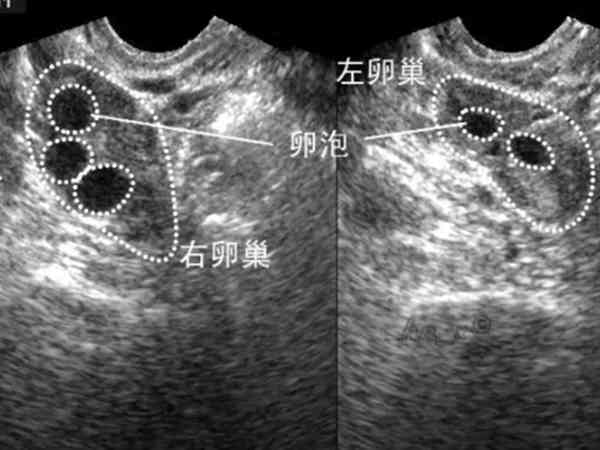

監測卵泡已經四次了,7月10日末次月經,7月18日有卵泡,大小為1.1*0.8,7月21日卵泡大小為1.2*1.0,7月24日長到了1.9*2.1,是個優勢卵泡,昨天再測,大夫說可能是之前那個排掉了,也可能是萎縮了。我昨天也有自己在家測排卵試紙,測到強陽,今天轉弱。請問如何確定是排了還是萎縮了?請問做陰超能準確的看出來嗎?做陰超是能夠準確的看出來優勢卵泡是萎縮了還是排出來了,因為B超監測卵泡發育是最簡單直接的方式,並且優勢卵泡萎縮後會在原來大小上變小並塌陷,而優勢卵泡排出陰超就會看到卵巢上沒有任何的無回聲區,也不會再看到有囊性暗區存在。所以說,優勢卵泡不管是萎縮還是排出都是可以通過超聲準確看出來的。

卵泡萎縮是指卵泡發育長大後沒有排出,卵泡就會逐漸變小或者是萎縮。而正常情況下,卵泡發育成熟會破裂排出卵子,稱為排卵。不管是優勢卵泡萎縮還是排出卵子都是可以通過陰超準確看出來的。下面就為大家介紹一下卵泡萎縮與排出的區別: